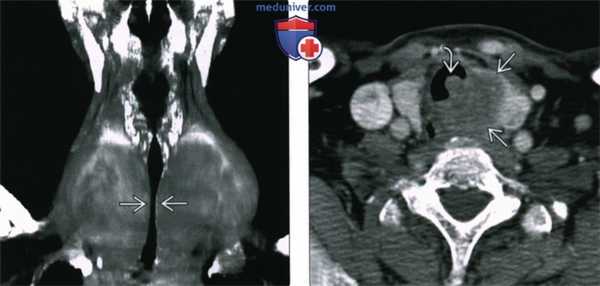

(Слева) Виртуальная КТ-бронхоскопия, просвет трахеи в норме. Обратите внимание на мембранозную часть трахеи. Томограмма ориентирована так, что врач смотрит в каудальную сторону, в направлении карины.

(Справа) Виртуальная КТ-бронхоскопия. Выраженный стеноз трахеи с неправильными контурами, вызванный формированием грануляционной ткани на уровне трахеостомы.

(Слева) Коронарная трехмерная реконструкция у пациента с многоузловым зобом. Определяется поперечный протяженный, стеноз трахеи, контуры которой остаются гладкими. Причиной стеноза является внешнее давление.

(Справа) КТ с КУ, аксиальная проекция у пациента с одышкой и осиплостью голоса. Больной страдает сосочковым раком левой доли щитовидной железы. Образование прорастает в шейную часть трахеи. Опухолевый узел, расположенный в просвете трахеи, вызывает сужение дыхательных путей.